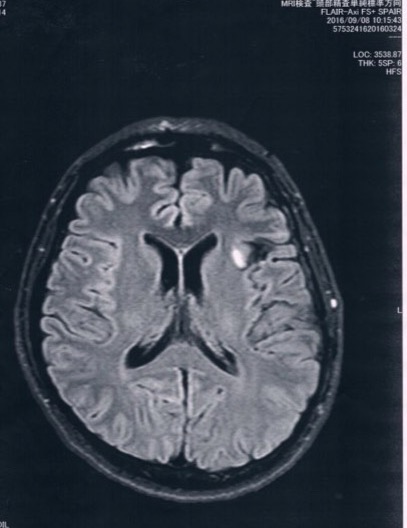

MRI検査の結果、半年前や一年前と比べても変化は無し!

残っている腫瘍は悪性転化していませんでした。

今回2016/9/8(手術後27か月)のMRI画像

今回の画像の方が、腫瘍がクッキリ写っているように見えるけど、

コントラストの違いだと思う。

びまん性星細胞腫グレード2を患ってます。